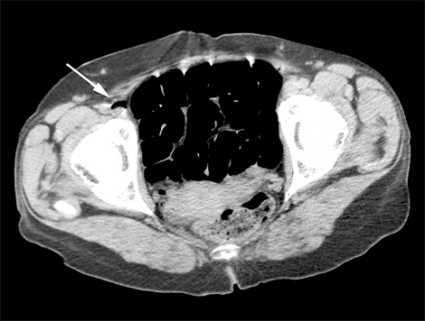

Vid litteratursökning senare samma dag återfanns ett mycket snarlikt fall av cerebral luftembolisering [1]. DT-undersökningarna granskades på nytt. Som tidigare nämnts fanns luft intrahepatiskt, men den här gången noterades luft även i vena femoralis på höger sida (Figur 2) samt i mindre kärl i glutealregionen på höger sida och i båda sidors ovarikakärl. Misstanke fanns även om luft i mesenterialkärlen. På DT av skallen återfanns intrakraniellt belägen luft i flera kärl, främst parietooccipitalt på vänster sida (Figur 3) men även högt frontalt bilateralt.